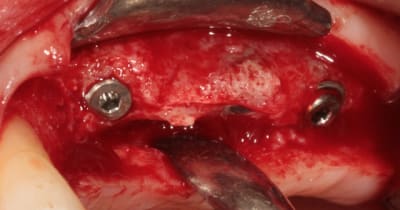

Bonjour mes CHERS AMIS, ouverture à 5 mois, et comme vous êtes sympas, je fais un lambeau (la patiente me pardonnera)

deux trois photos pour montrer que crédulité et optimise ne vont pas de pair....

ah ! oui, le VITAL OS à super bien fonctionné ici.

c'est bien mené, on voit nettement la différence entre l'avant et l'après, surtout le volume des crêtes.